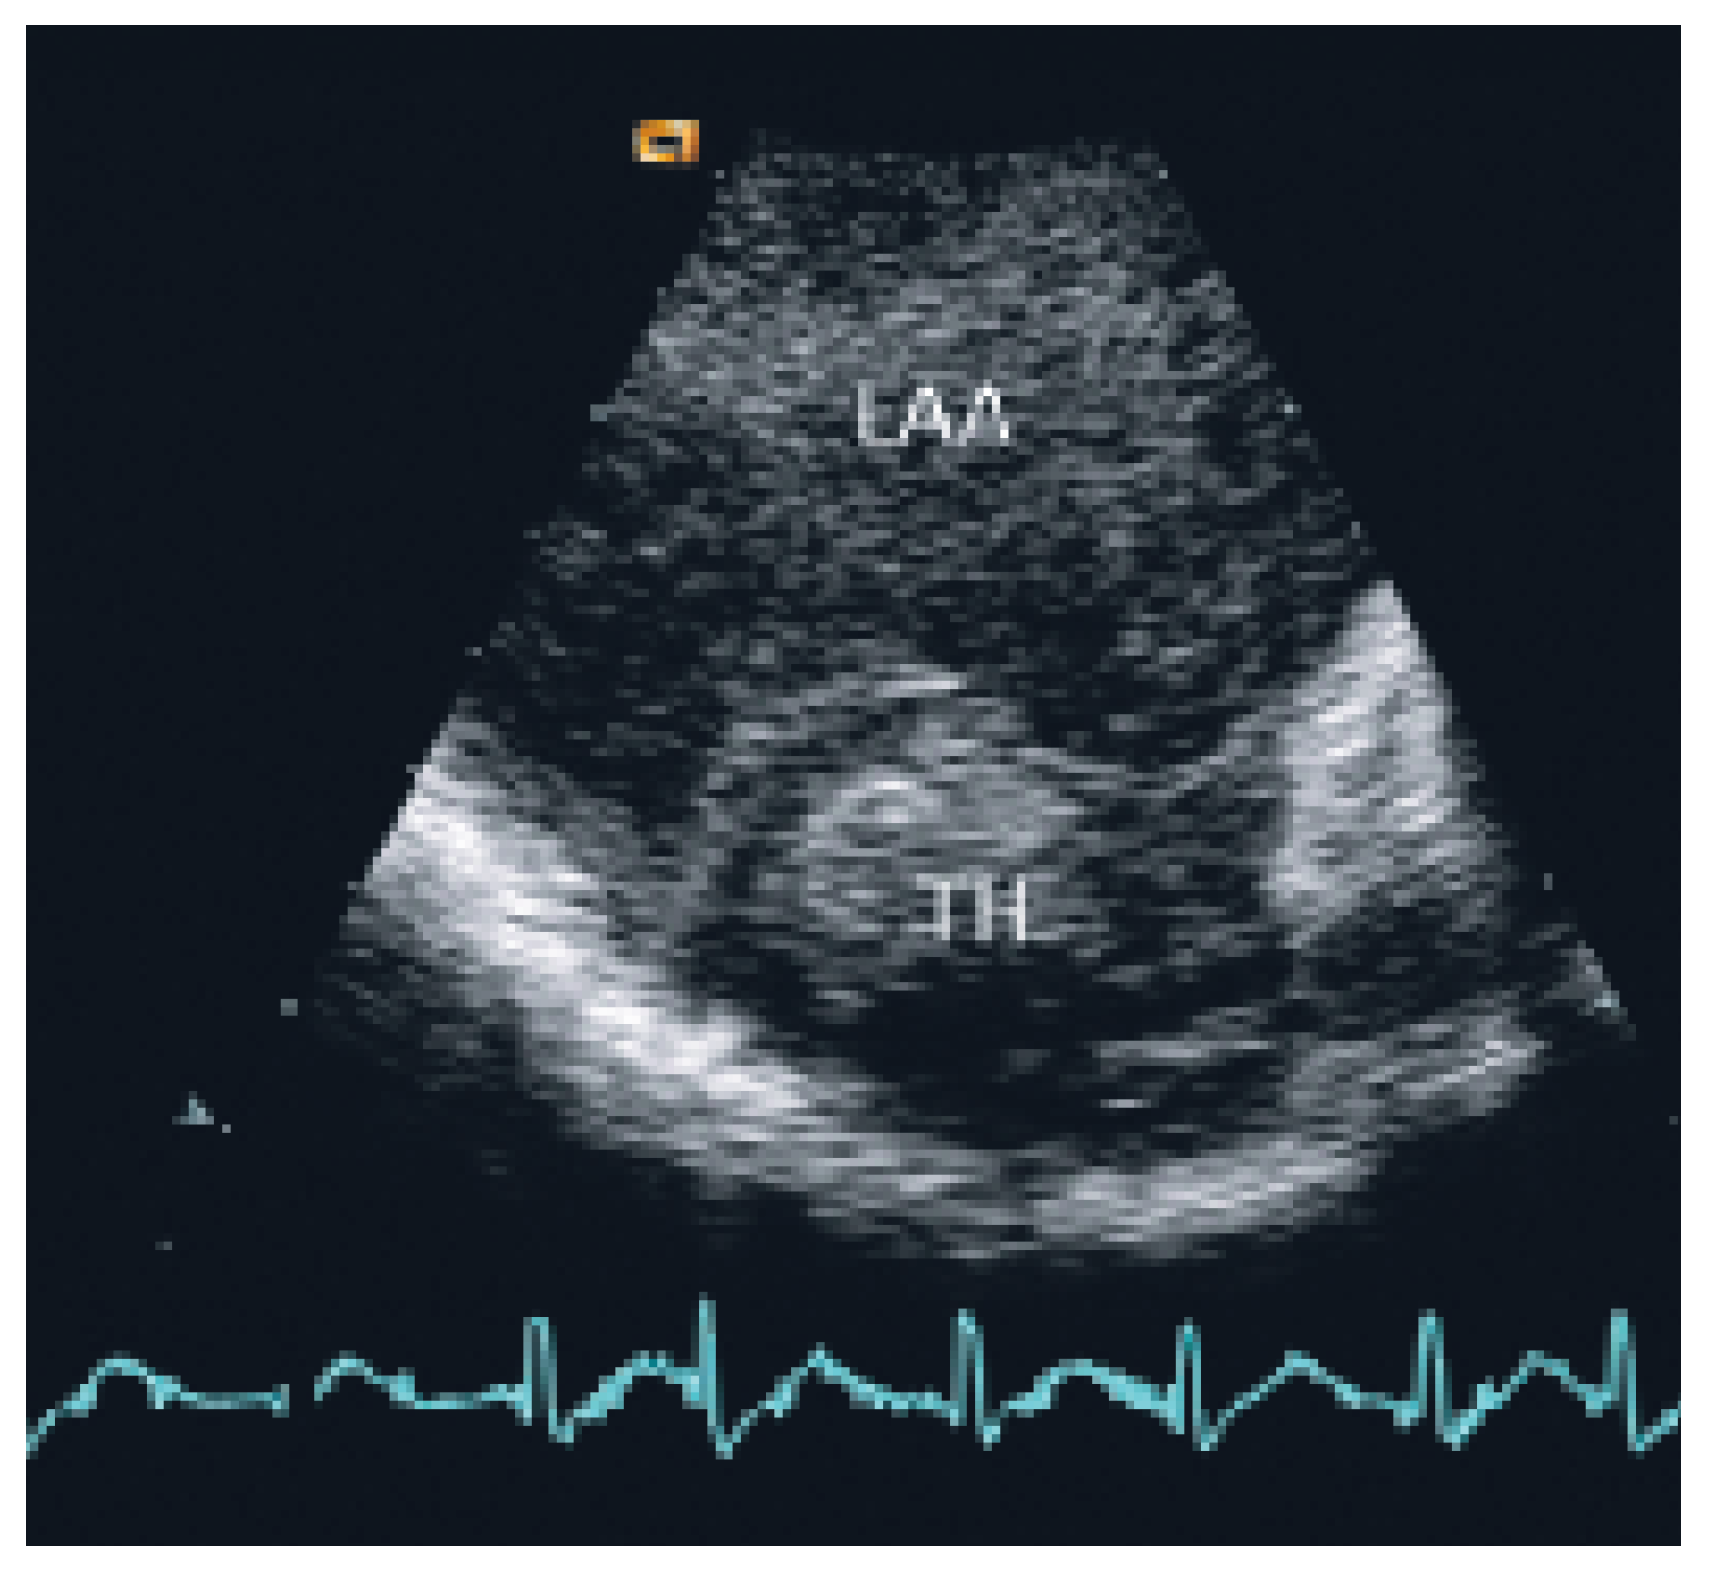

At TEE severe spontaneous echocontrast in the left atrium (Figure 2) and a thrombus (2.7 cm × 3.5 cm) in the left atrial appendix were present (Figure 3). There was no evidence of impairment of the beleaflet mechanical valve (mean transvalvular gradient 4 mm Hg). Anklebrachial pressure index was abnormal (0.5), and duplex ultrasounds showed acute thromboembolic occlusion of right superficial femoral artery.

As cited in Hurst’s memories [1] “… giant left atrium is defined as one that touches the right lateral side of the chest wall. The condition is caused by rheumatic mitral valve disease and atrial fibrillation is always present …”. This case illustrates the pivotal role of echocardiography in defining and quantifying this pathology and the associated thromboembolic risk. TTE and particularly TEE allowed to assess the magnitude of the giant left atrium (Figure 1), the presence of spontaneous contrast and intracardiac thrombus (Figure 2 and 3), the presence of normal functioning of the mechanical valve prosthesis, and the occurrence of a new apical dyskinesia compatible with the diagnosis of acute myocardial infarction [2].

Figure 3. Transoesophageal echocardiography shows a thrombus in the left atrial appendix. LAA = left atrial appendix; TH = thrombus.